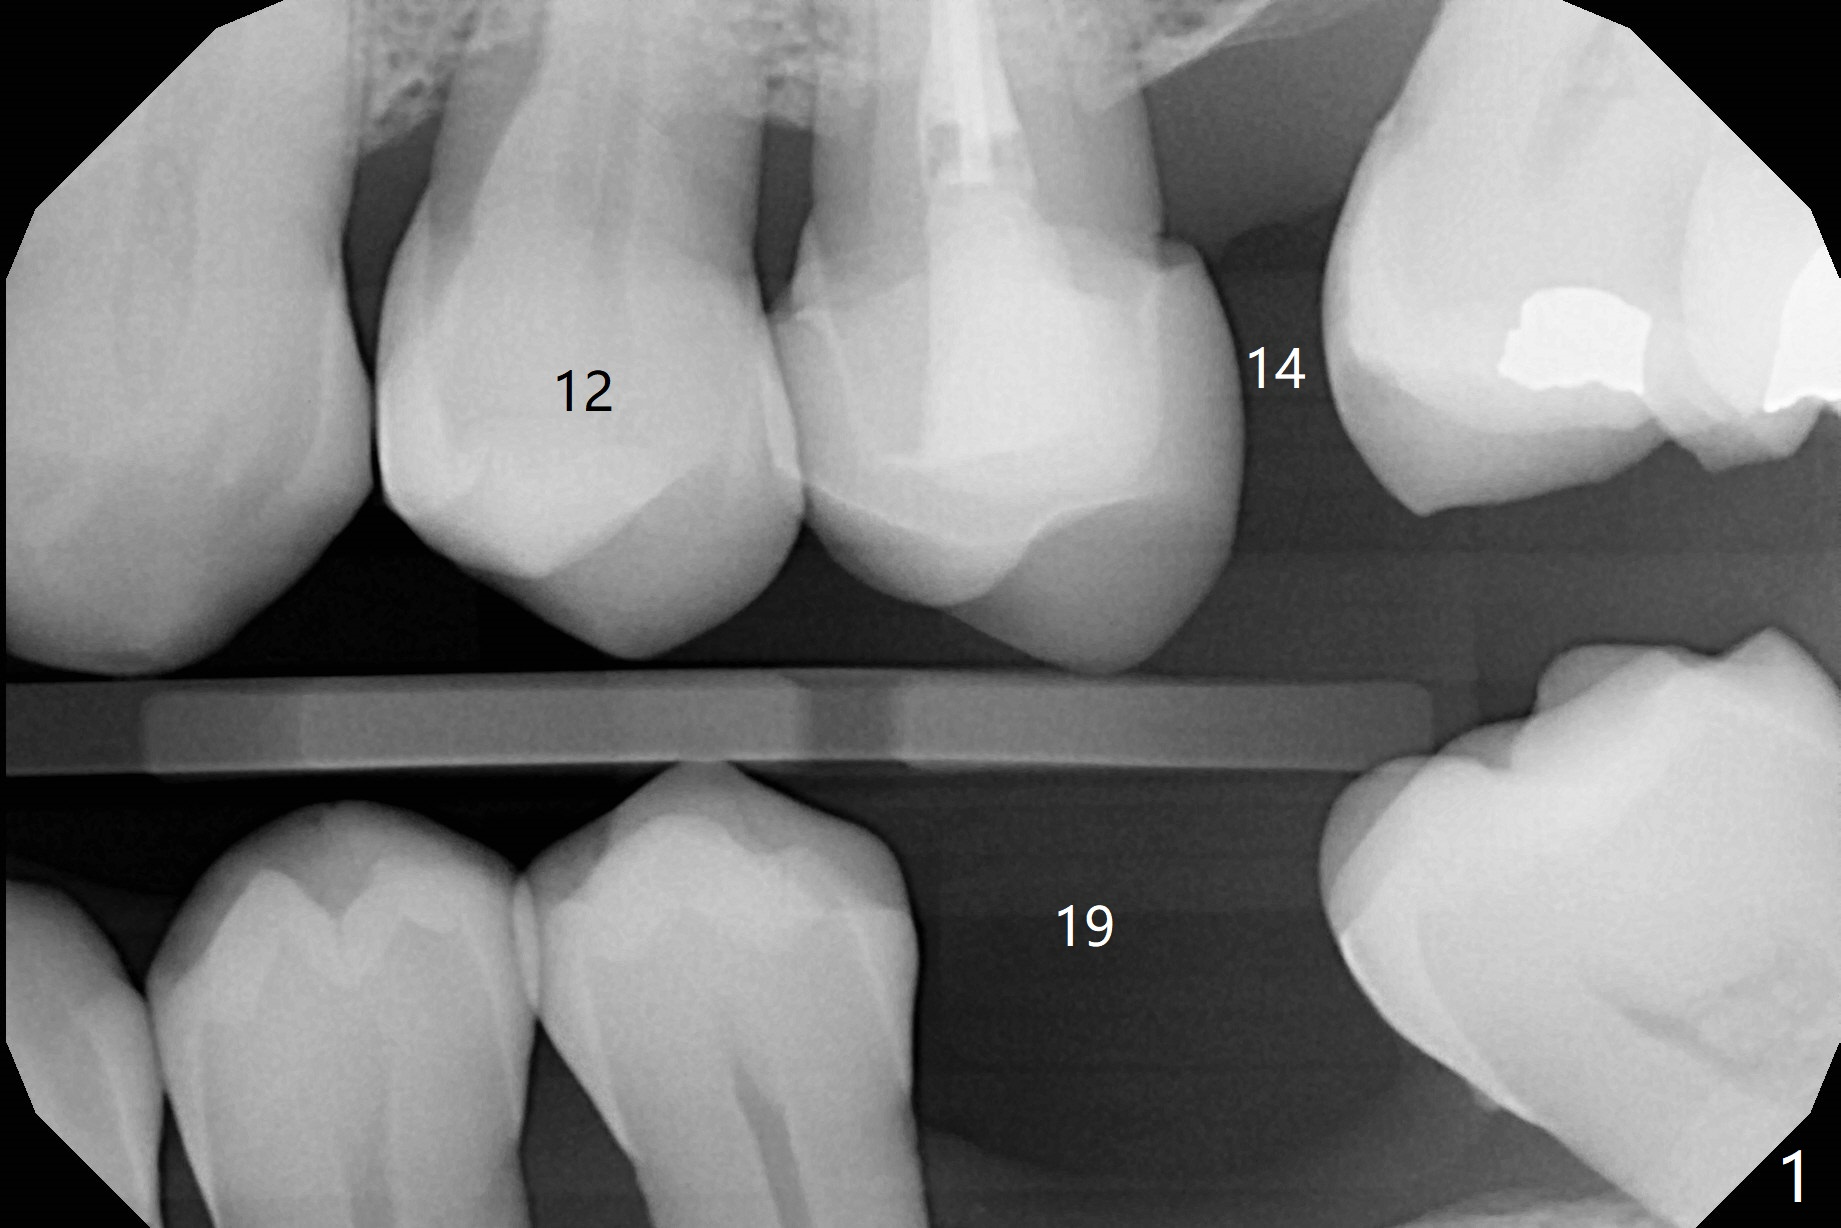

Tooth Crack: Emergency

A 57-year-old woman presents to clinic when her ex-dentist is too busy to place immediate implant for a crack tooth at #12 (Fig.1,2). Free hand placement is scheduled in 2 days. Because of loss of several molars, the occlusal clearance for the immediate provisional should be sufficient (Fig.3). Prepare 4 or 4.5 x17 or 20 mm Tatum implants. Take photos of the crack before surgery.